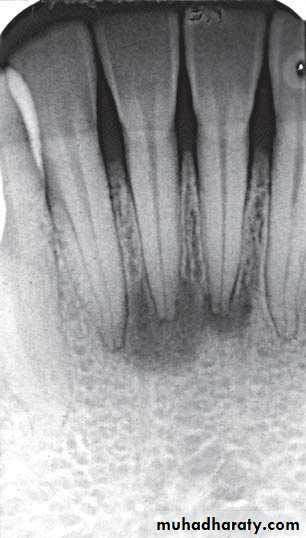

Radiographic features:

Location: Apex of involved tooth / Cervically up the tooth root.Periphery: Ill defined / Well defined, with gradual blending of normal trabecular pattern into sclerotic pattern.

Internal structure: *Early lesion→ no radiographic change.

*Widening of PDL space at the apex.

*A mixture of sclerosis (radiopaque) and rarefaction (radiolucent).

* ↑se bone formation → periapical sclerosing osteitis.

*↑se bone resorption → periapical rarefying osteitis.

No change

Effects on surrounding structures:

* Losing of lamina dura at the apex.* Regions of sclerotic bone around apex.

* External apical root resorption.

* Inflammatory periosteal reaction (new bone formation in max. S.) → halo shadow.